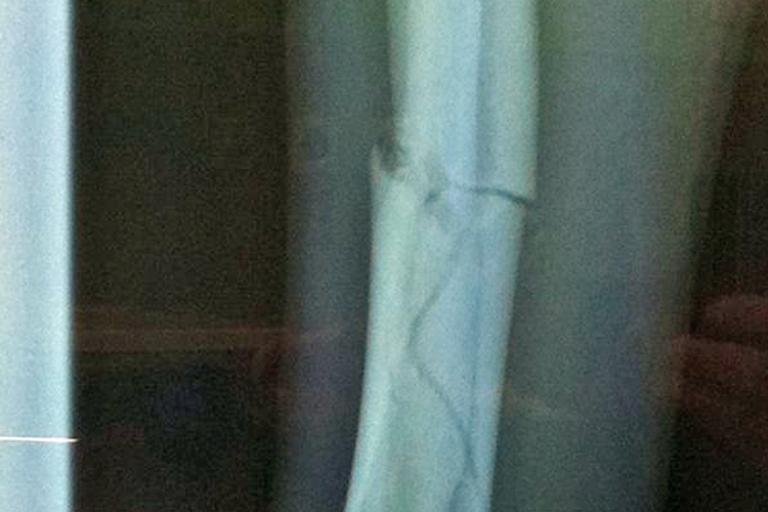

"Oh das sieht böse aus", schilderte Streckensprechen Bernd Fulk die Geschehnisse. Das Motorrad war nach einem Highsider auf der Strecke liegengeblieben, was den Abbruch zur Folge hatte. Vos war ebenfalls benommen liegengeblieben und wurde noch an der Strecke von den Helfern erstversorgt. Anschliessend ging es in die Klinik von Magdeburg. Der Niederländer hatte sich das Schienbein gebrochen. Nach einer Operation ist er nun wieder zuhause in Oss und regelt vom Sofa aus seine Geschäfte. "Mir geht’s wieder ganz gut", versichert er. Vos, der bis letztes Jahr noch in der IDM Superbike unterwegs war, war als Führender der Niederländischen Meisterschaft nach Oschersleben gekommen. Ganz abgeschrieben hat Vos den Titel noch nicht.